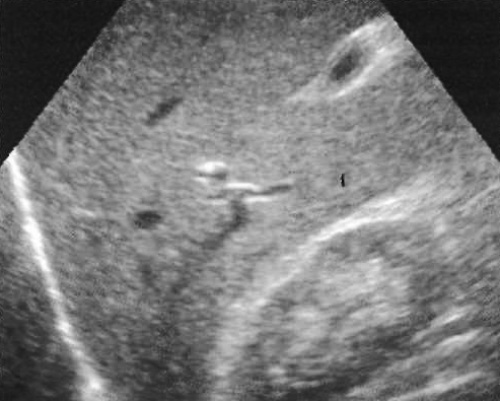

Фото 4. Холелитиаз. А – УЗИ в продольной плоскости, пациент находится в положении лежа: стрелкой обозначен мелкий эхогенный очаг без тени, локализованный в шейке желчного пузыря. В – УЗИ того же пациента в положении лежа на правом боку: стрелками обозначены камни в желчном пузыре

Следует применять максимальную частоту, чтобы обеспечить достаточное проникновение ультразвука в правом (датчик с частотой ≥ 3,5 МГц). При исследовании желчного пузыря следует использовать гармонические методики (фото 5).